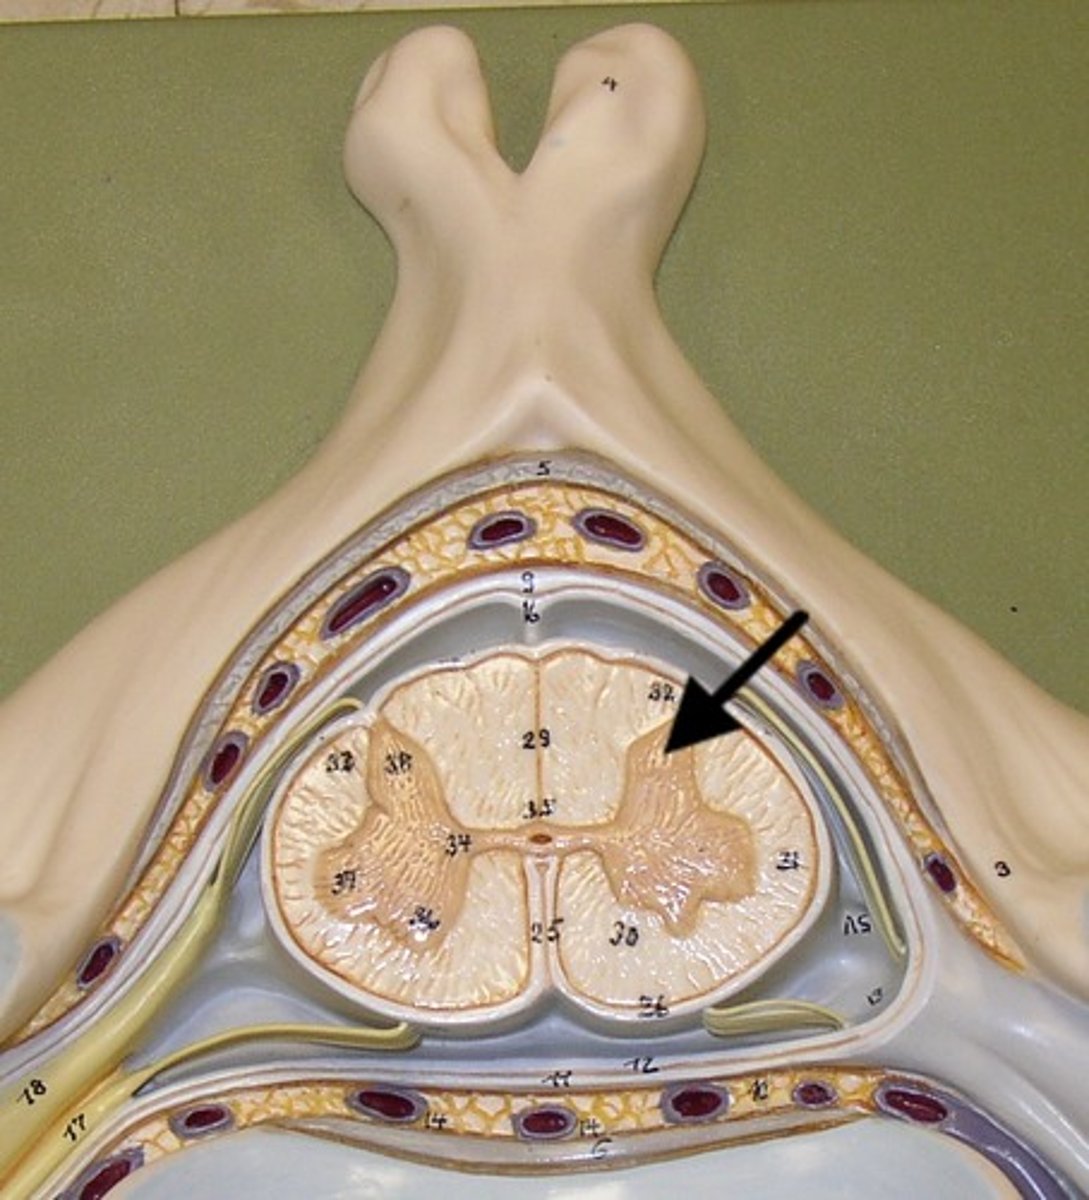

arachnoid mater

middle layer of the meninges

B on model

subarachnoid space

a space in the meninges beneath the arachnoid membrane and above the pia mater that contains the cerebrospinal fluid

pia mater

the delicate innermost membrane enveloping the brain and spinal cord.

denticulate ligaments

extensions of pia mater that secure cord to dura mater laterally